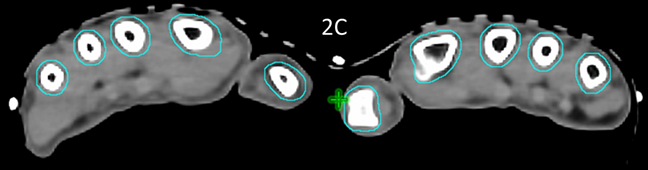

These volumes were then approved by the RO. The target volume was intended to be the joint including synovium with prescription to cover the PTV with 95% of the prescription dose. (Figure 2)

Figure 2 Contouring and dosimetry.

Figure 2A Axial planning CT slice through zero plane of knee in Figure 1A showing PTV (blue volume indicated by white arrow) as 2 mm expansion of CTV which was an auto contour of the bone.

Figure 2B Axial planning CT slice through zero plane showing dosimetry as colour wash set at 2.5Gy level. Notice excellent conformity to PTV and homogeneity within the PTV and sparing of soft tissues that may not have been spared by a 3DCRT approach.

Figure 2C Axial planning CT slice through zero plane of hands in Figure 1B showing PTV (blue volume) as 2 mm expansion of CTV which was an auto contour of the bone.

Figure 2D Axial planning CT slice through zero plane showing dosimetry as colour wash set at 2.5Gy level. Similar to Figure 2B, notice excellent conformity to PTV and homogeneity within the PTV while sparing the palms.